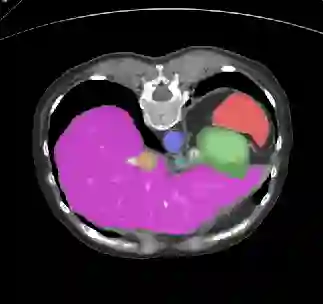

Recently, deep learning methods have achieved state-of-the-art performance in many medical image segmentation tasks. Many of these are based on convolutional neural networks (CNNs). For such methods, the encoder is the key part for global and local information extraction from input images; the extracted features are then passed to the decoder for predicting the segmentations. In contrast, several recent works show a superior performance with the use of transformers, which can better model long-range spatial dependencies and capture low-level details. However, transformer as sole encoder underperforms for some tasks where it cannot efficiently replace the convolution based encoder. In this paper, we propose a model with double encoders for 3D biomedical image segmentation. Our model is a U-shaped CNN augmented with an independent transformer encoder. We fuse the information from the convolutional encoder and the transformer, and pass it to the decoder to obtain the results. We evaluate our methods on three public datasets from three different challenges: BTCV, MoDA and Decathlon. Compared to the state-of-the-art models with and without transformers on each task, our proposed method obtains higher Dice scores across the board.